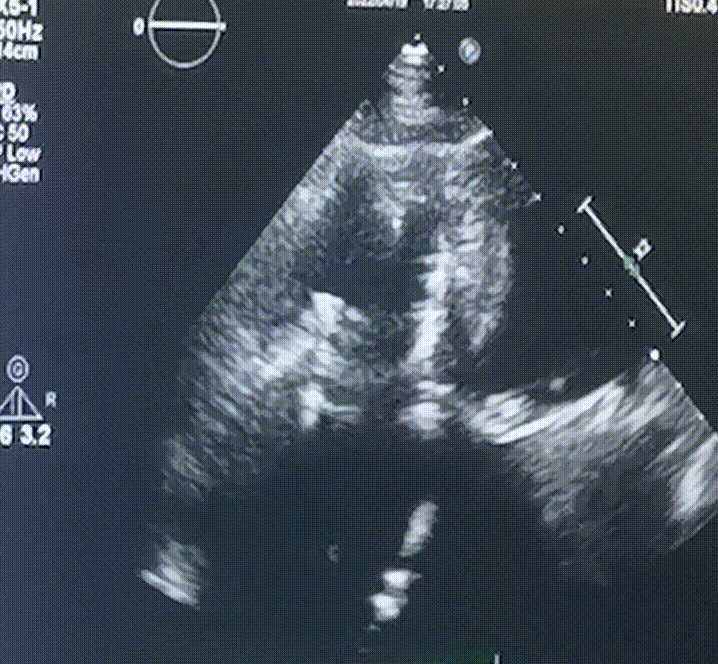

術前超聲提示:

1.右心、左房明顯增大;

2.二尖瓣人工機械瓣功能正常,無瓣周漏;

3.三尖瓣環(huán)巨大擴張,收縮期瓣葉對合不攏,收縮期三尖瓣房側見大量反流信號,反流面積15-20cm²,TRVmax:240cm/s,跨瓣壓差:23 mmHg。

圖1.術前超聲